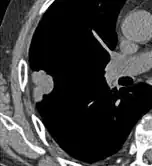

- A lung nodule abutting a pulmonary cyst is a rare finding, yet indicating cancer.[9]

- Bubble-like lucencies in the nodule indicate cancer:[9]